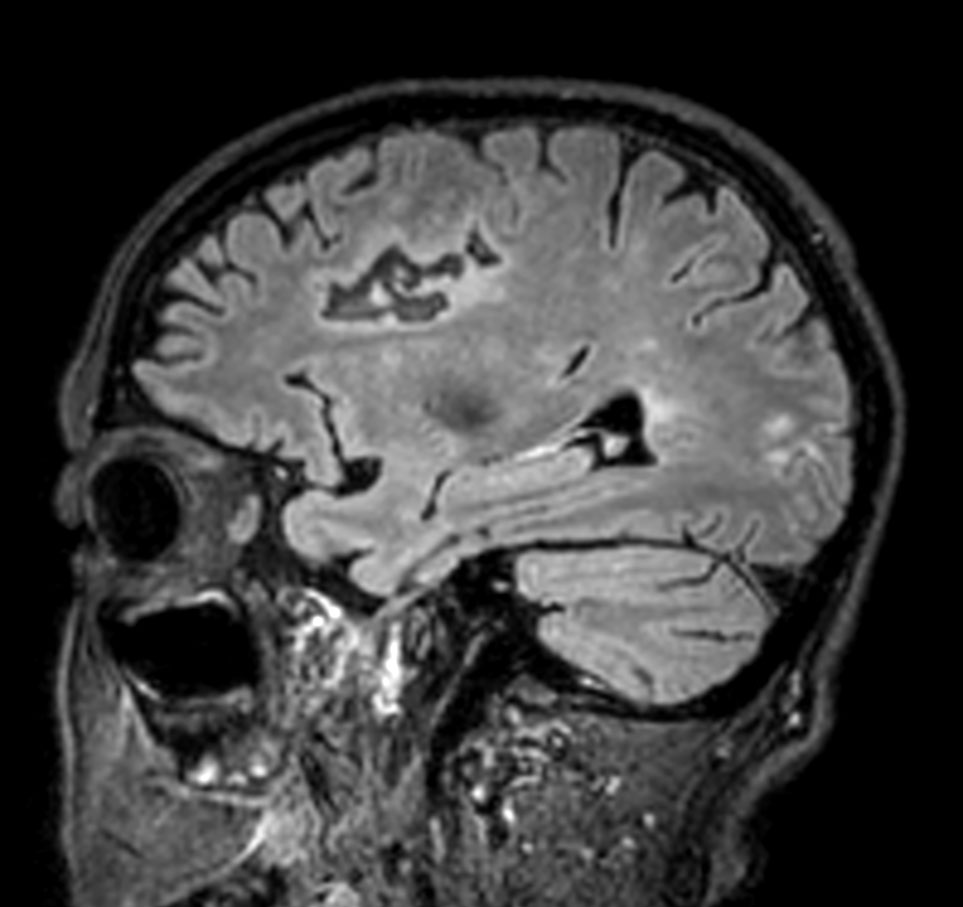

Patient with multiple brain lesions. The ExamCard includes Compressed SENSE to accelerate the entire exam and techniques for motion reduced imaging (MultiVane XD), 3D imaging to acquire high resolution data in multiple directions, 3D susceptibility weighted imaging (SWIp), DWI with EPIC Brain to bring down any residual distortion and Computed DWI to generate synthetic high b-value images.

3D T2w FLAIR Compressed SENSE

-

3D T2w FLAIR (reformat) Compressed SENSE